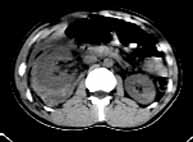

男性,22岁,车祸,被汽车方向盘压伤右季肋部,局部见长5cm的伤口。

ct表现:右侧肾上腺肿大,密度增高,右肾上极段肿胀,密度增高,右侧肾周间隙积血。

ct诊断:右肾及肾上腺挫裂伤